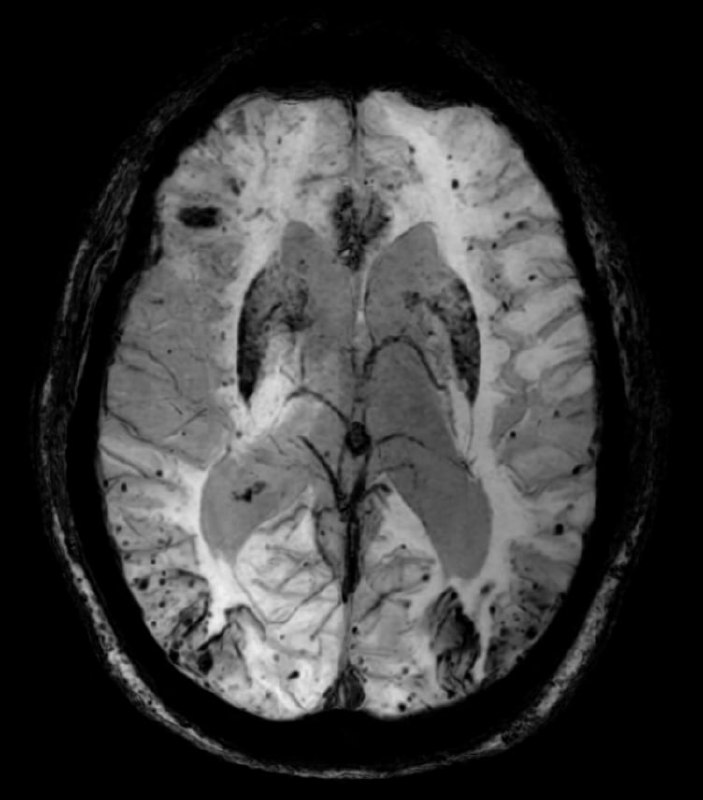

"Красивая" картина церебральной амилоидной ангиопатии у пожилого пациента на SWI (изображения, взвешенные по магнитной восприимчивости):

1. Множественные микрокровоизлияния с периферическим (юкстакортикальным) типом распространения.

2. Мультифокальный поверхностный сидероз ЦНС (пластинчатые, повторяющие контуры извилин участки выпадения сигнала на SWI).

3. Генерализованная церебральная атрофия, которую видно по расширению желудочков и субарахноидальных пространств.

4. Отсутствующие, либо единичные мелкие кровоизлияния в глубоких отделах мозга (стволе, мозжечке, таламусах и покорковых узлах/структурах), что характерно для геморрагической микроангиопатии, вызванной длительно существующей артериальной гипертензией.